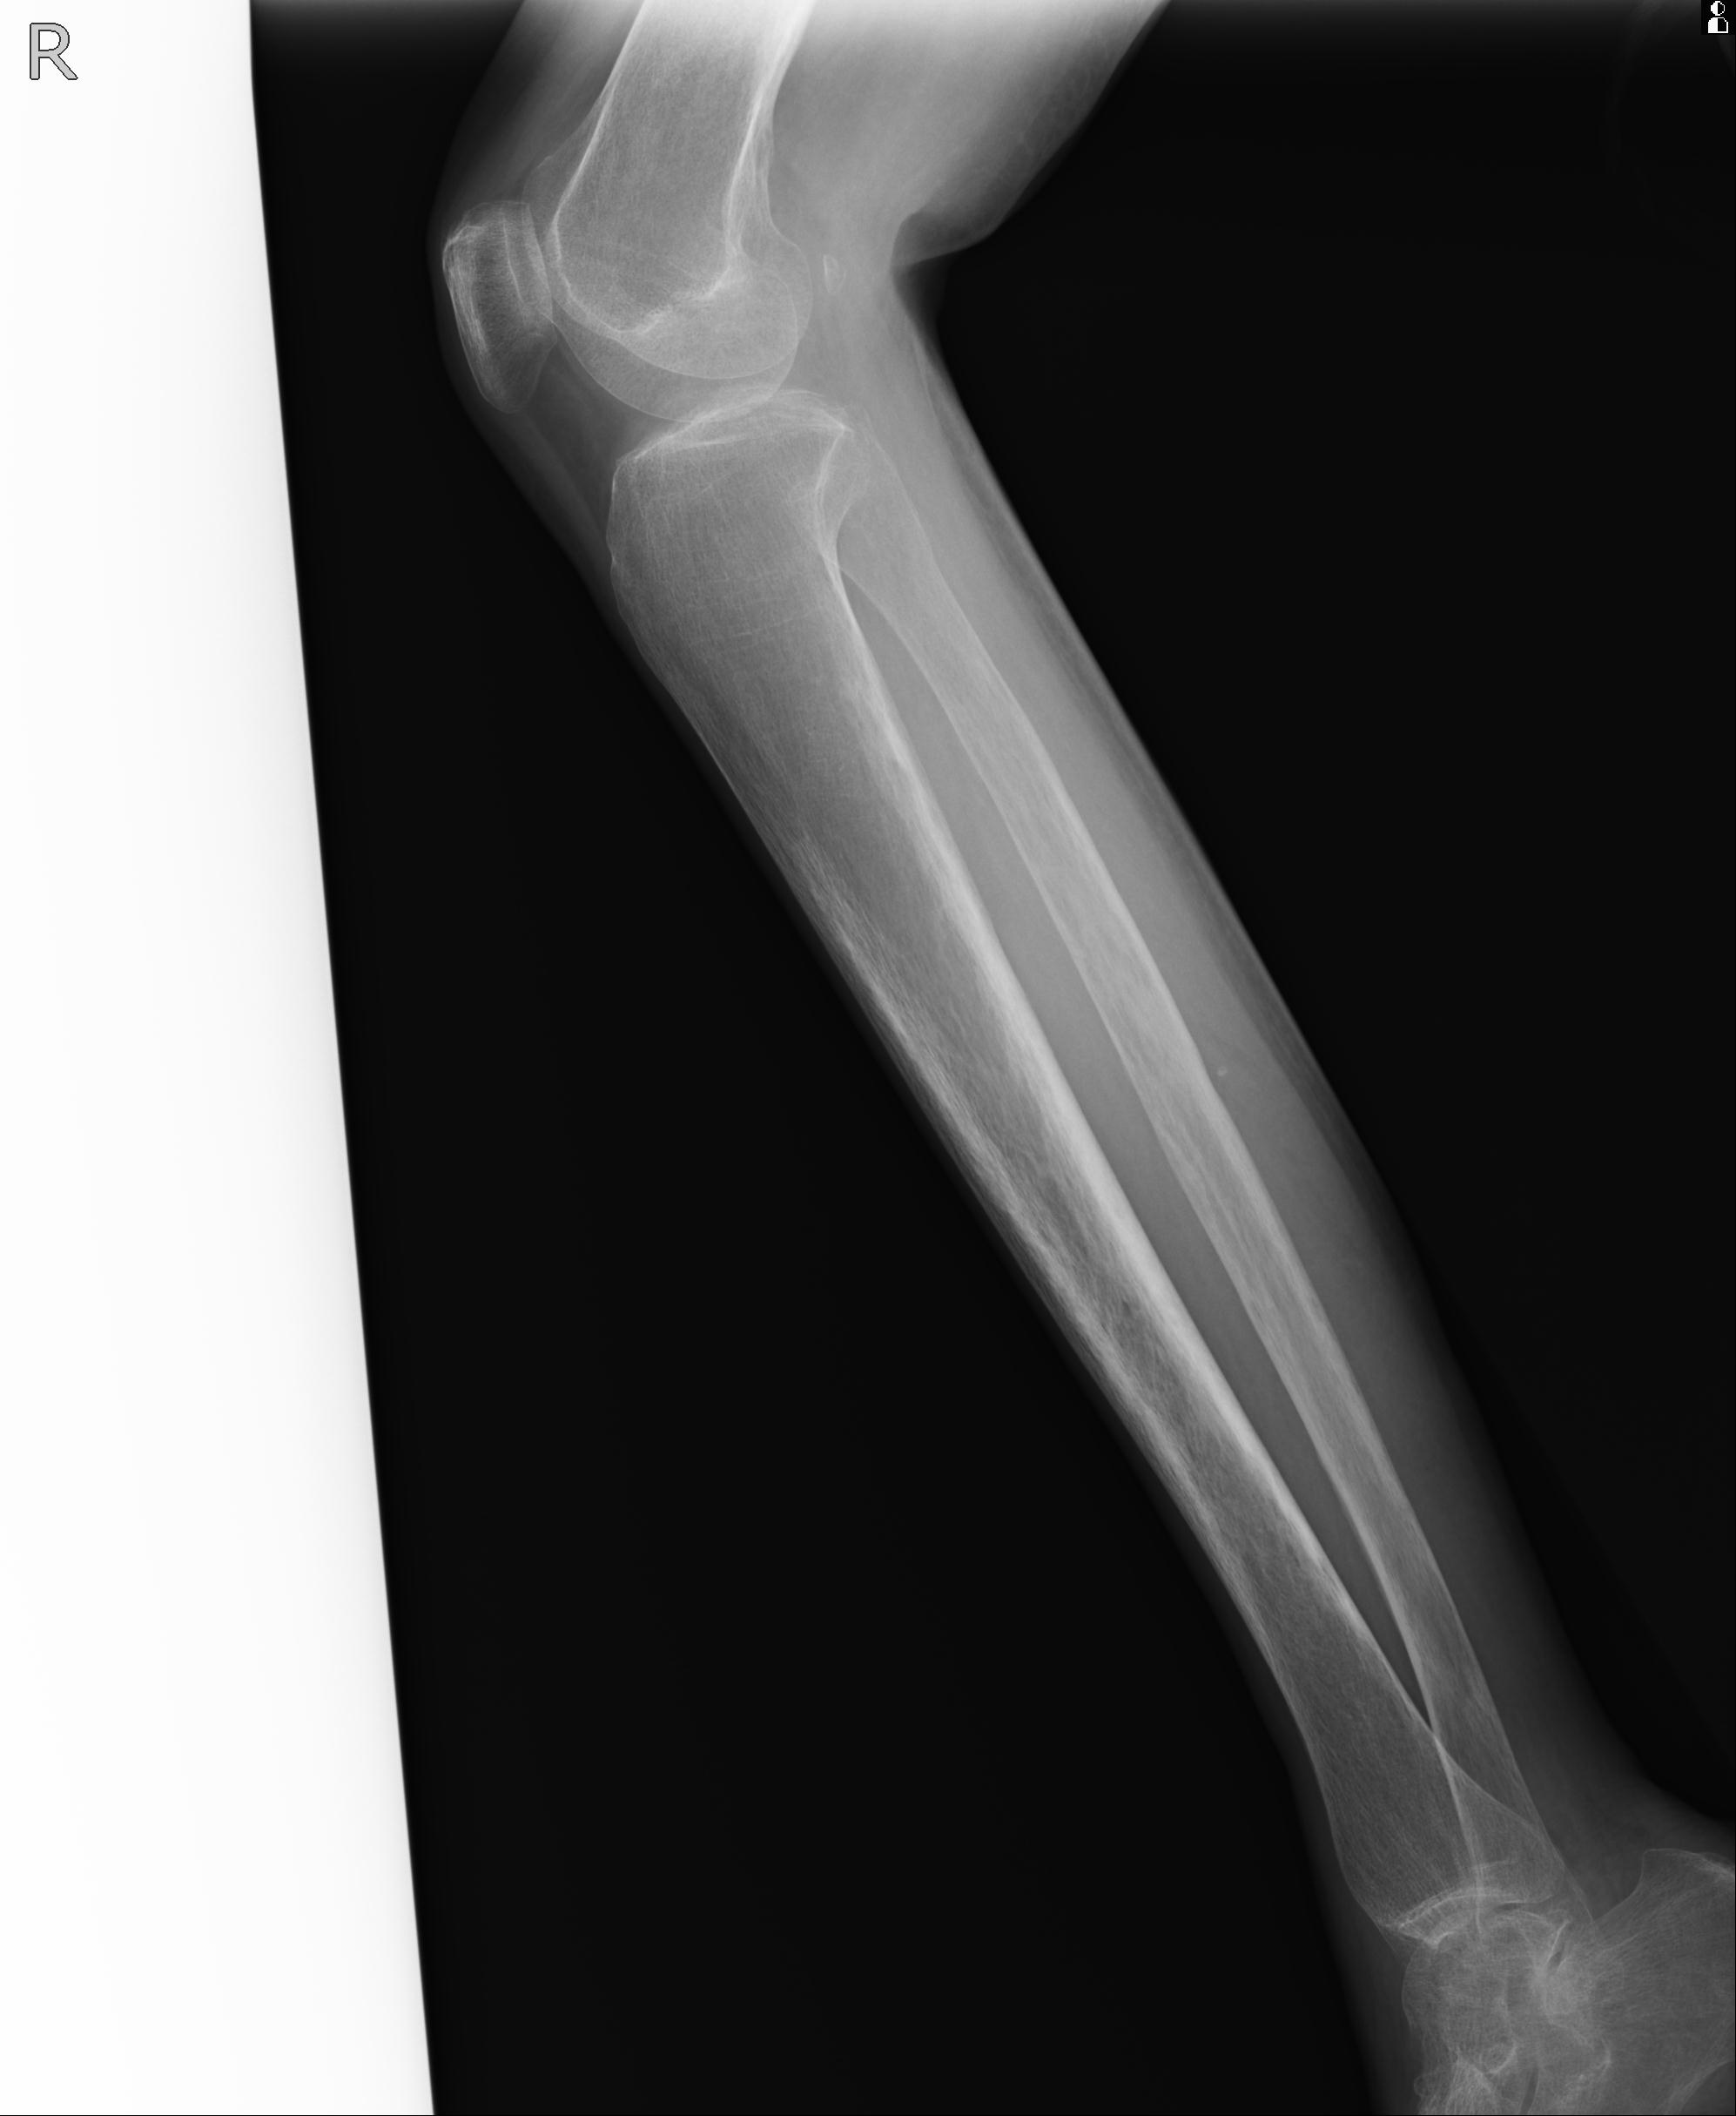

102803 1/12(キウスなし) 1/27 左下腿 4R 30歳女性 左脛骨軸内釘